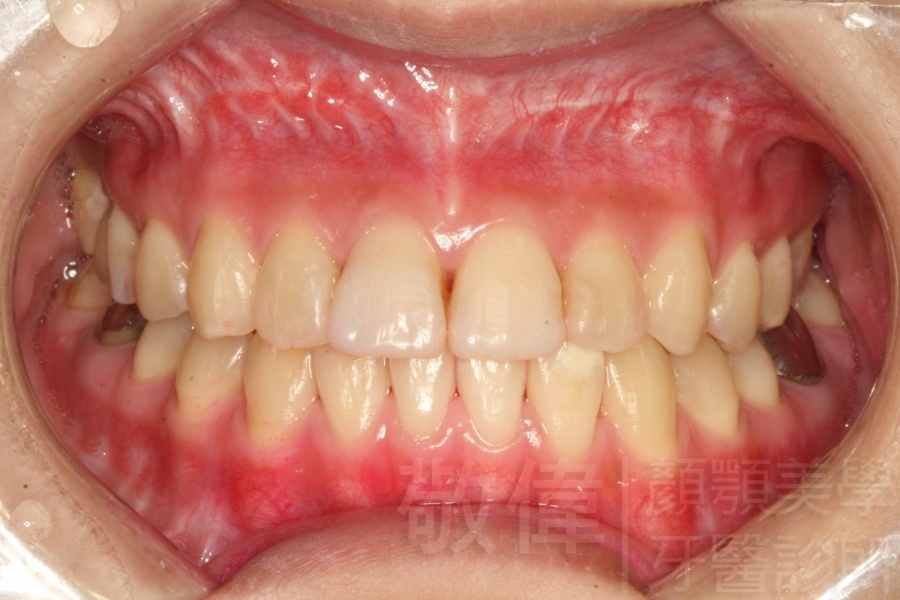

變臉矯正,原來戽斗妹跟大歪臉變成自信正妹

經由本院3D數影X光影像儀分析、與3D齒顎顏矯正技術,再配合口腔顎面正顎專科醫師施以正顎手術治療,雙方共同合作,使患者臉部外觀有很好的改善,大歪變小歪,產生了天南地北的大改變,她的人生也整個變得不一樣。

因為矯正與正顎手術的配合,使「戽斗妹」變成了「陽光正妹」,完全的改變了她的人生,在面對各種場合、與人交際都散發出自信微笑。所以,奉勸家長,如果小朋友有臉顎畸型的問題,應該考慮配合做這種簡單、安全、有效的正顎手術。